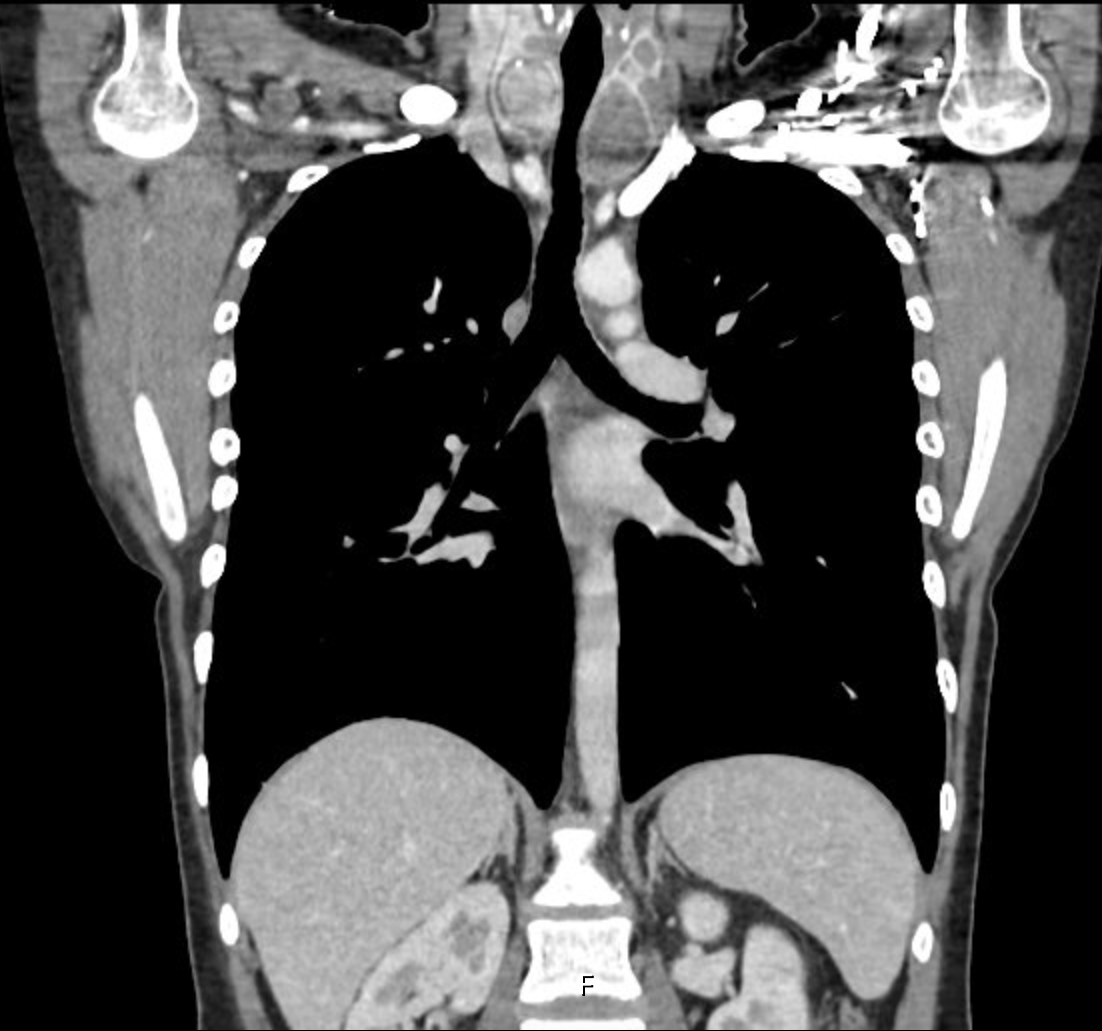

Kontrastlı toraks bilgisayarlı tomografi sonucu: Her iki tiroid lobunda en büyükleri sağda 12 mm ,solda 20 mm çapında hipodens nodüller mevcuttur. Soldaki nodüller toraksa da uzanım göstermektedir(Resim 3). Sağ akciğer alt lobda plevraya yakın yerleşimli multi septalı ince duvarlı hava kistleri mevcuttur(Resim 4). Kliniği ile beraber değerlendirilmesi önerilir.

![]() |

Resim 3: Kontrastlı toraks bilgisayarlı tomografi